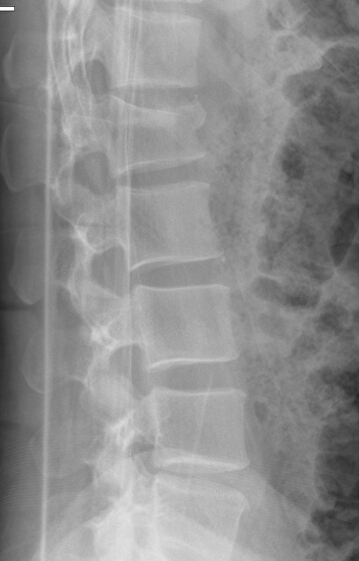

Based on this image, does this patient have a new or old fracture?

old fracture (black is whack, white is right)